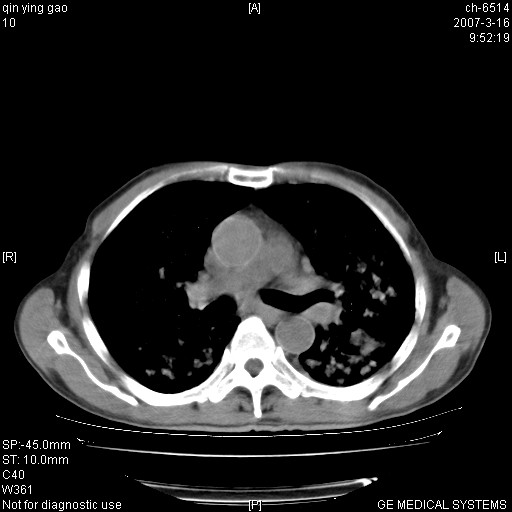

男,64岁.乏力2个月,畏寒、发热1月余。体重下降。血沉加快,白细胞不高。

双肺以中上肺野为著斑片状.结节壮密度增高影 左上肺前段可见小类圆钙化灶 纵隔淋巴结无明显肿大

3.主动脉弓.冠状动脉钙化形成

两肺弥漫分布的斑片状影,部分融合,左肺及纵隔淋巴结见钙化影,考虑1。tb,2。肺泡细胞癌,建议查痰检

中上肺野密布棉团状影,以胸膜下区为界,边缘模糊,可能是小叶或腺泡渗出及实变。全肺野弥漫分布网线样影及细小粟粒样影,可能是细支气管炎及间质内炎症。综合分析应首先考虑气道播散性感染,而肺内多处斑点性钙化,强烈提示陈旧结核复发并支气管播散。建议详细讯问病史

病变以两肺上野为著,部分病灶有钙化,纵隔窗显示病灶有新老不一,这个首先和结核脱不了干系,还有部分病灶有融洽的倾向,肿瘤也不能完全排出